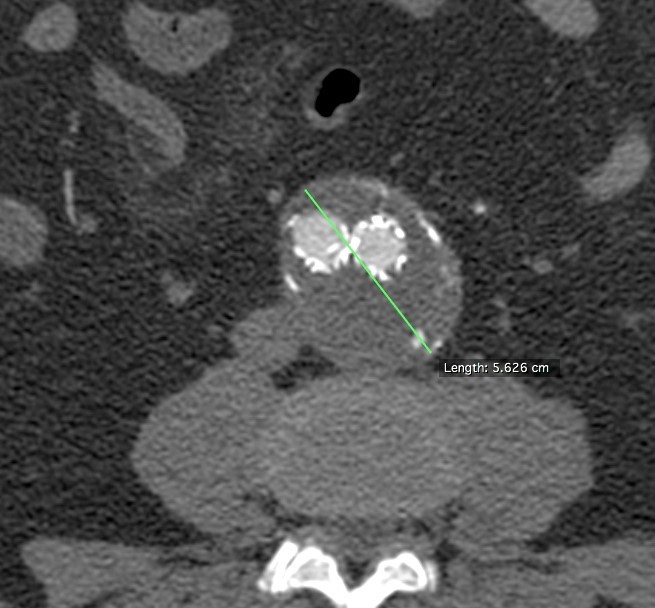

Τα ανευρύσματα της κοιλιακής αορτής πρέπει να αντιμετωπίζονται όταν η διάμετρος τους ξεπερνάει τα 5 εκατοστά. Τα ανευρύσματα των λαγονίων όταν η διάμετρος ξεπερνάει τα 3-3,5 εκατοστά. Τα παραπάνω ανευρύσματα τις περισσότερες φορές χρειάζεται να αντιμετωπίζονται ταυτόχρονα λόγω στενής γειτνίασης των αγγείων αυτών.

Επιπρόσθετο ανώνυμο φωτογραφικό υλικό

από την αντιμετώπιση ανευρυσμάτων της κοιλιακής αορτής και των λαγονίων αρτηριών

από το προσωπικό μου αρχείο στα Πανεπιστημιακά Νοσοκομεία Λάρισας και Ιωαννίνων

• Περιπτώσεις ανευρυσμάτων λαγονίων αρτηριών